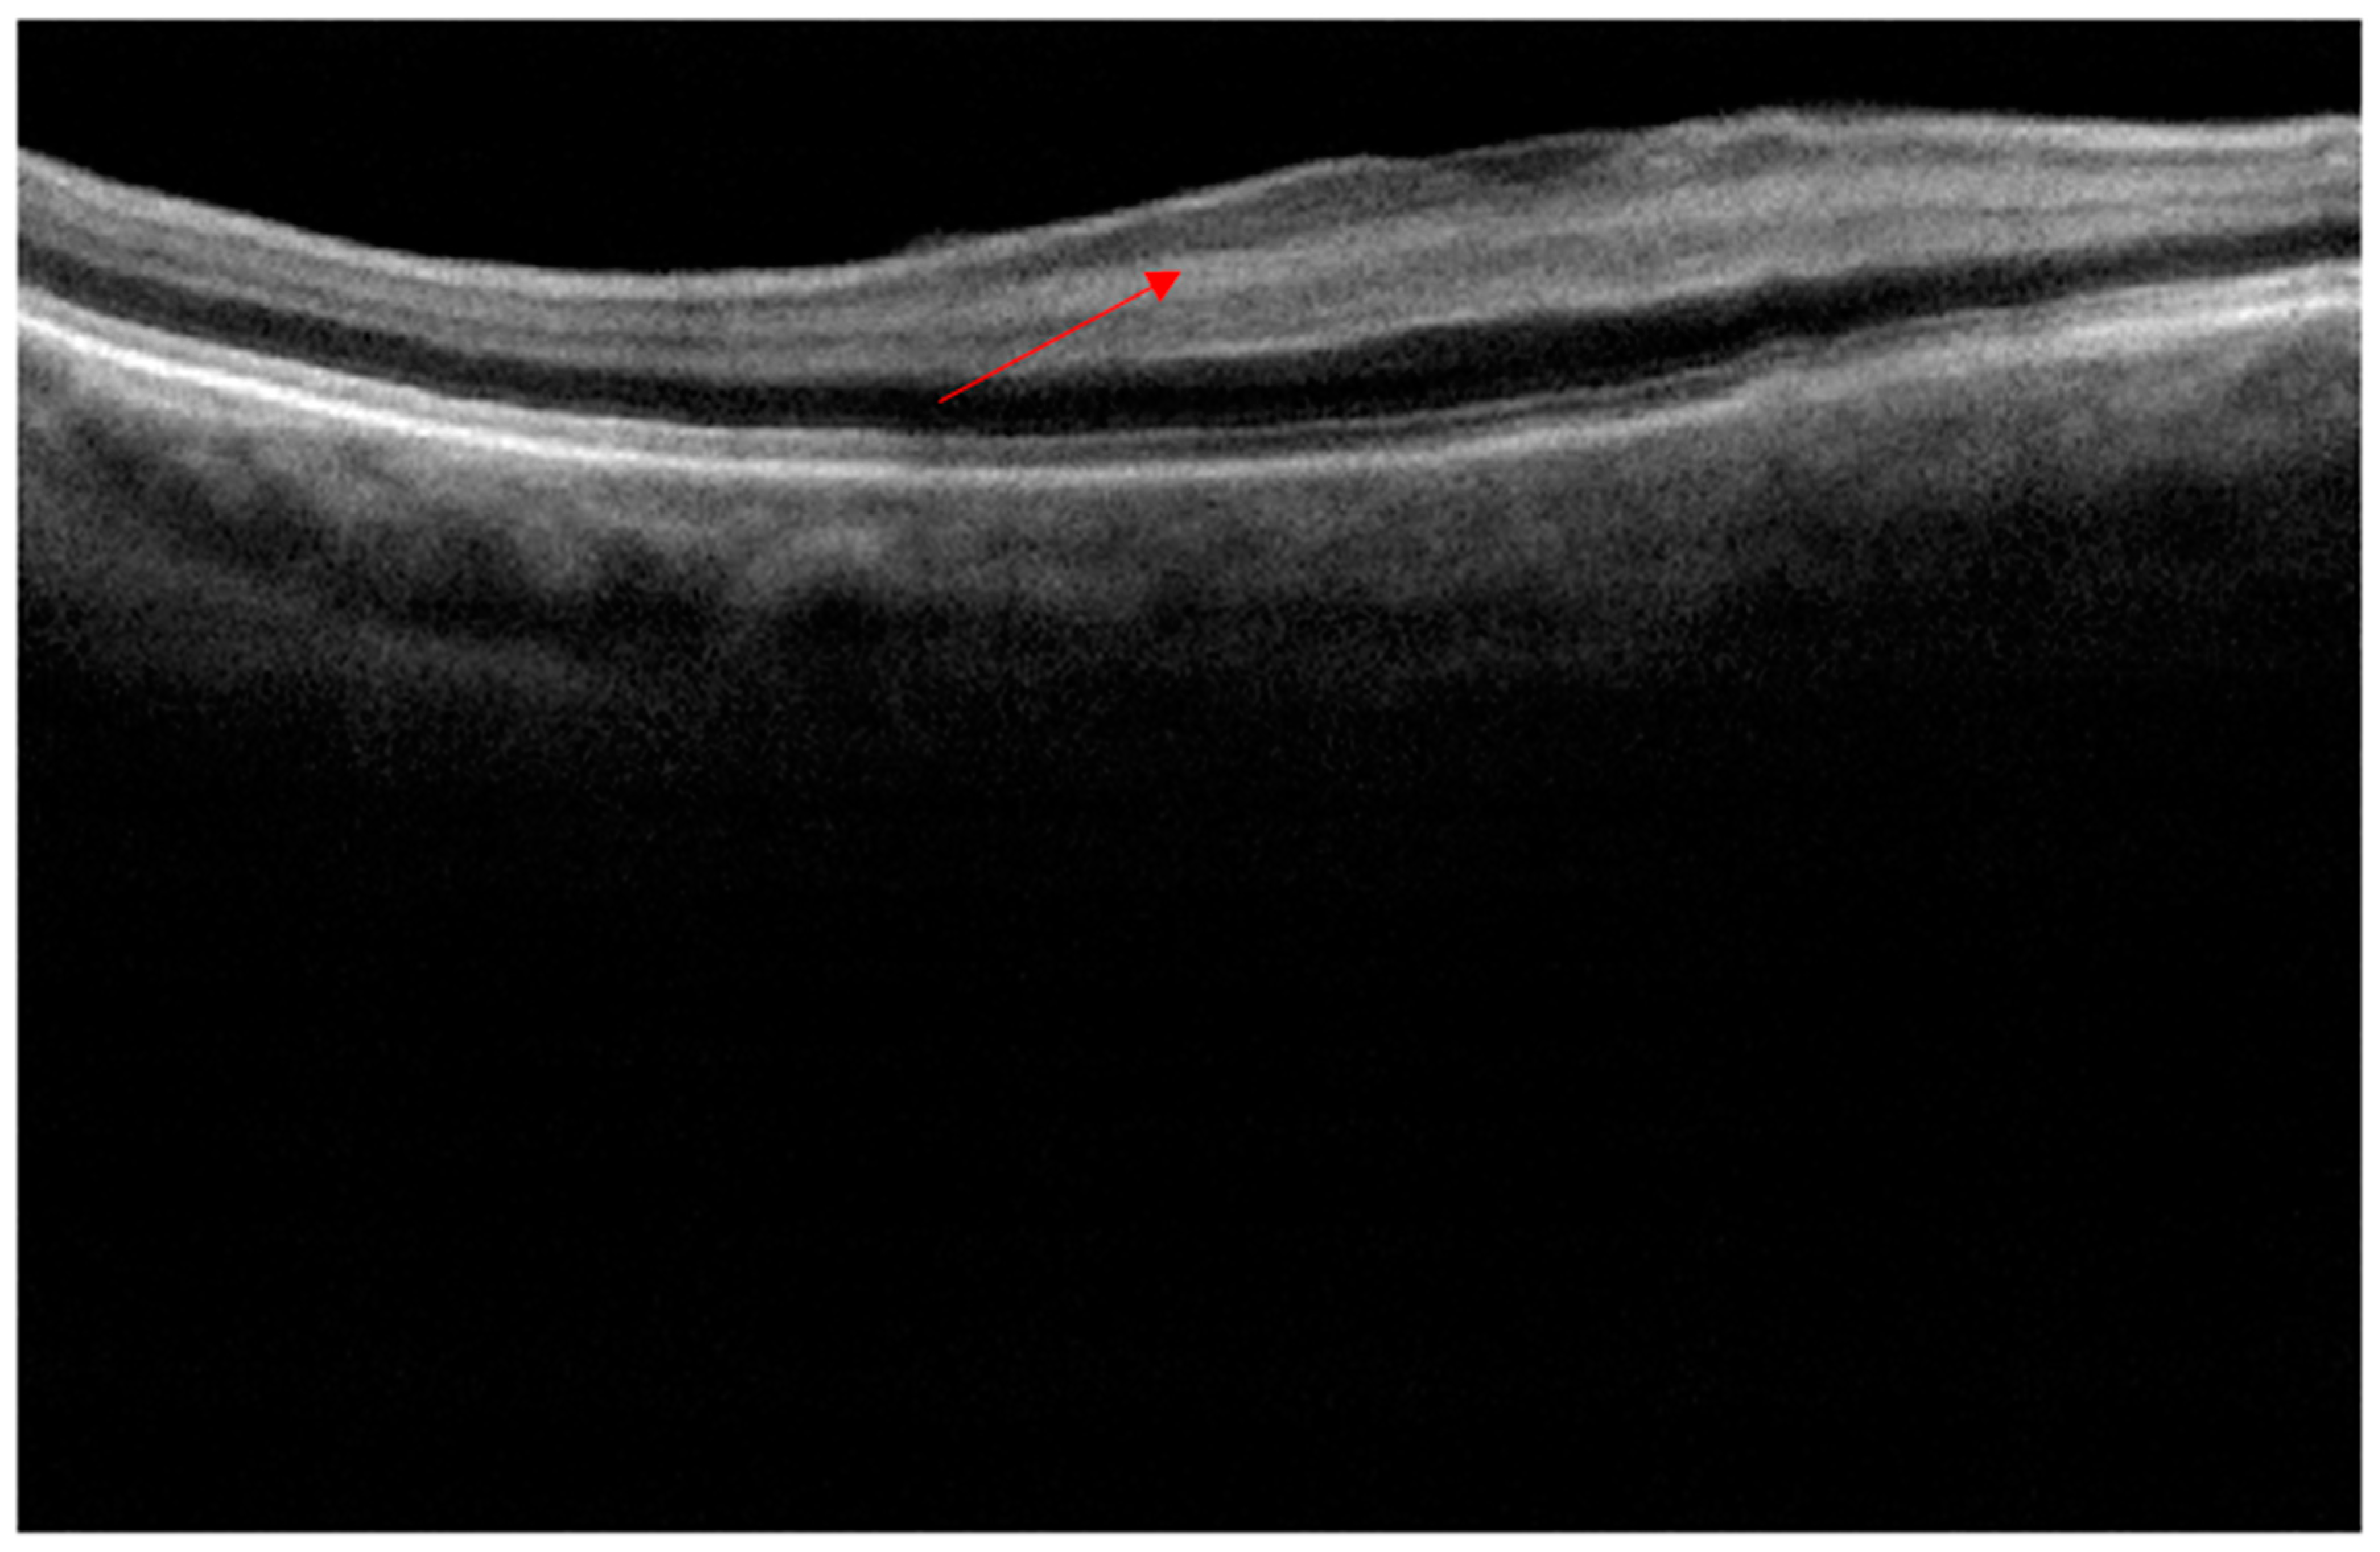

The patient was reviewed on the first postoperative day as part of the surgeon’s routine practice. Upon removal of the pad, the acuity measured finger counting only, with a central scotoma, but fully preserved peripheral vision. Clinical examination including IOP and dilated fundoscopy was entirely normal, with no relative afferent pupillary defect (RAPD) or bruising. An OCT scan (Figure 2), performed with a different scanner from the preoperative scan, was difficult to perform due to poor fixation, but demonstrated a clear increased signal in the INL compared to the scan (Figure 1) performed five months previously. At one week, acuity had gradually recovered to 6/9 unaided but required considerable searching for the chart, the patient describing “a central small island of vision in a sea of darkness”.

Figure 2. Day one postoperative OCT cross section showing total loss of the negatively enhancing inner nuclear layer, replaced by a highly reflective band marked by a red arrow.